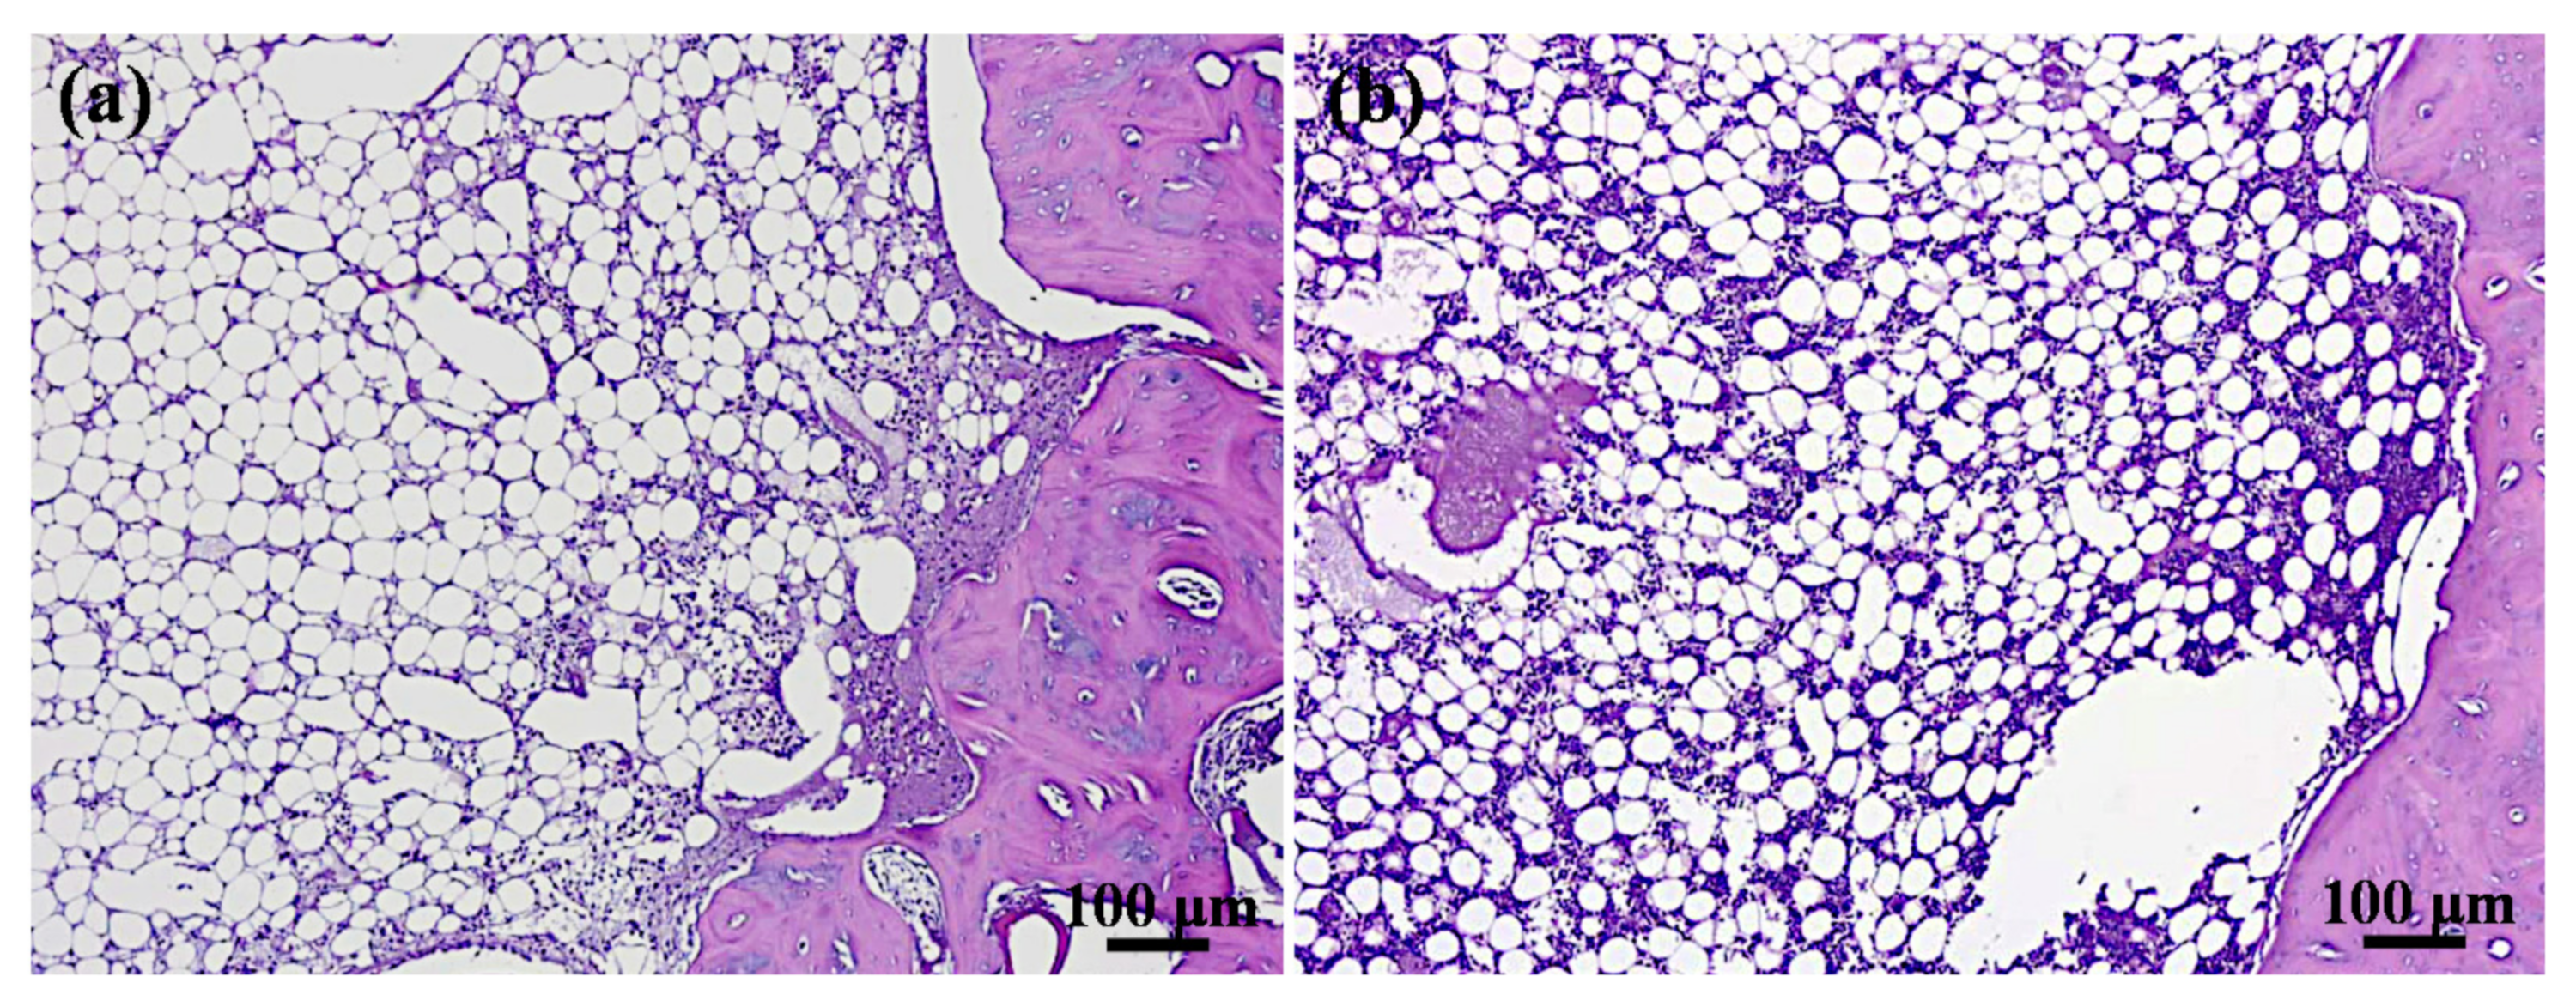

3.4. Bone Tissue Reaction Features

| HT-3 (n = 10) | Autogenous Bone Group (n = 10) | p Value | |

|---|---|---|---|

| Polymorphonuclea | 1.2 ± 1.8 | 0.8 ± 1.1 | 0.68 |

| Lymphocytes | 4.4 ± 0.9 | 3.6 ± 0.9 | 0.20 |

| Plasma cells | 0 | 0 | |

| Macrophages | 0 | 0 | |

| Giant cells | 0 | 0 | |

| Necrosis | 0 | 0 | |

| Neovascularization | 0 | 0 | |

| Fibrosis | 0.6 ± 0.5 | 0.6 ± 0.5 | >0.05 |

| Fatty infiltrate | 2.2 ± 0.5 | 2.4 ± 0.9 | 0.67 |